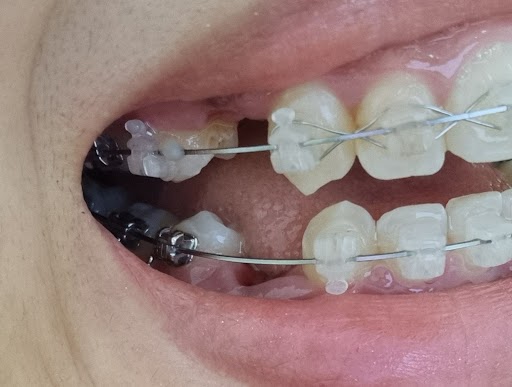

2022/08/16 발치한 자리 사진에 보이는 것이 좌측에 발치한 공간인데요

저번 포스팅에서도 얘기했듯이

생각했던 것 보다 치아 하나가

차지하고 있는 공간이 넓다는 것을 깨달았습니다.

저 사이 공간이 다 닫히고 배열이 완료되어야

비로소 교정이 끝나는 것일 텐데

얼마나 더 긴 시간이 남아있을까요?